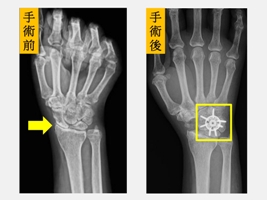

陳重宇醫師表示,傳統的融合術多以鋼釘或螺釘固定,依最新研究顯示,環狀鋼板能提供更佳的初期穩定性,提高骨頭癒合成功率,並讓病人更早開始復健,降低僵硬與肌力流失的風險。由於劉先生的症狀是手腕腫脹、活動受限和握力明顯下降,X光檢查顯示已進展至中後期病程,經醫療團隊充分討論後,劉先生接受「舟狀骨切除合併四角融合術(scaphoid excision and four corner fusion)」,並使用新型環狀鋼板固定,復原順利。